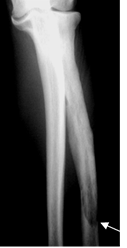

Fig 47. Enfermedad de Paget en fase lítica.

A: Rx AP. Zona lítica en el tercio distal del radio, con signo de la llama de vela.

El tercio medio del hueso esta engrosado y es esclerótico, por cambios de fase blástica.